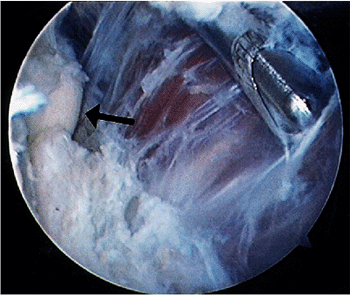

![]() |

Figure 2-11. A typical case example illustrating many of the techniques used in elbow arthroscopy. A,B: Radiographs of a patient with synovial osteochondromatosis. C,D:

Technique for posterior compartment surgery and establishing the appropriate position of the portal. The arthroscope is directed to the posterior compartment, where loose bodies are seen. A needle is introduced in the precise position that one estimates to be ideal for the portal to be established. E,F: After establishing the portal with a knife under direct vision, a grasping instrument is inserted to remove the loose body. The remaining loose bodies are similarly removed. G,H: The area of synovial osteochondromatosis that is adherent to the posterior aspect of the humerus at the edge of the olecranon fossa is osteotomized with a small, curved osteotome under direct vision. This is quicker and more efficient than using a bur or a small biting instrument, which tends to make the risk rather tedious. If the osteotomized piece is large, it can be fragmented for removal. |